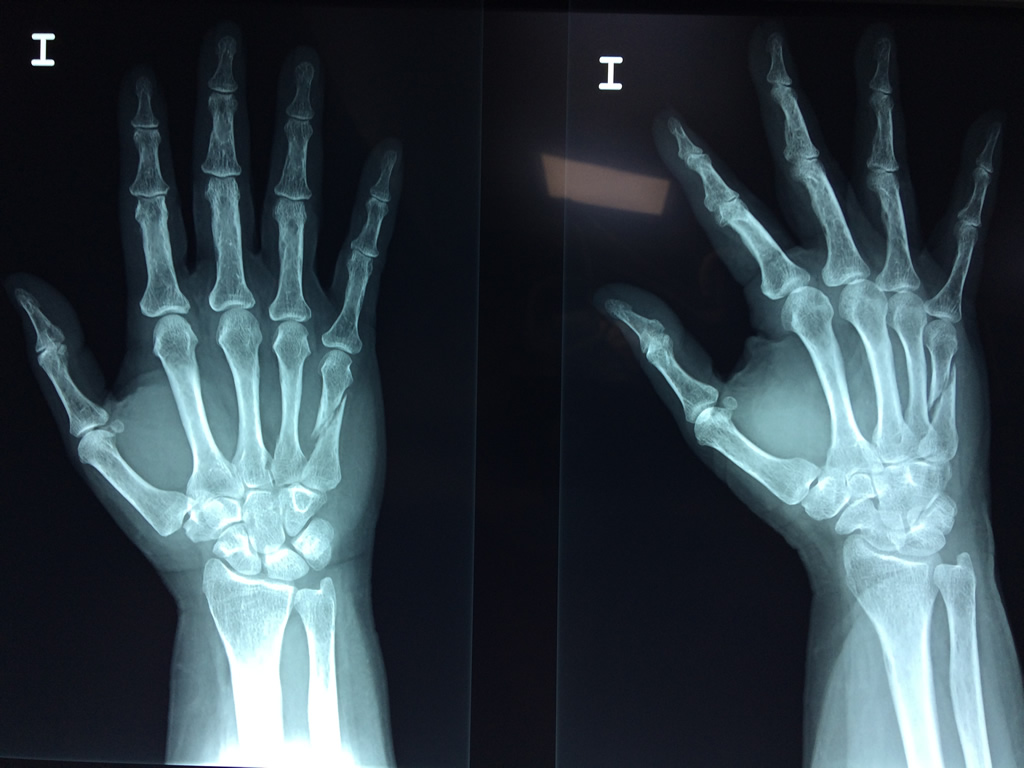

Cirugías de Muñecas

Los procedimientos más comunes en cirugía de la mano son aquellos destinados a reparar traumatismos, incluyendo lesiones de tendones, nervios, vasos sanguíneos, y articulaciones; huesos fracturados; y quemaduras, cortes, y otros daños de la piel.